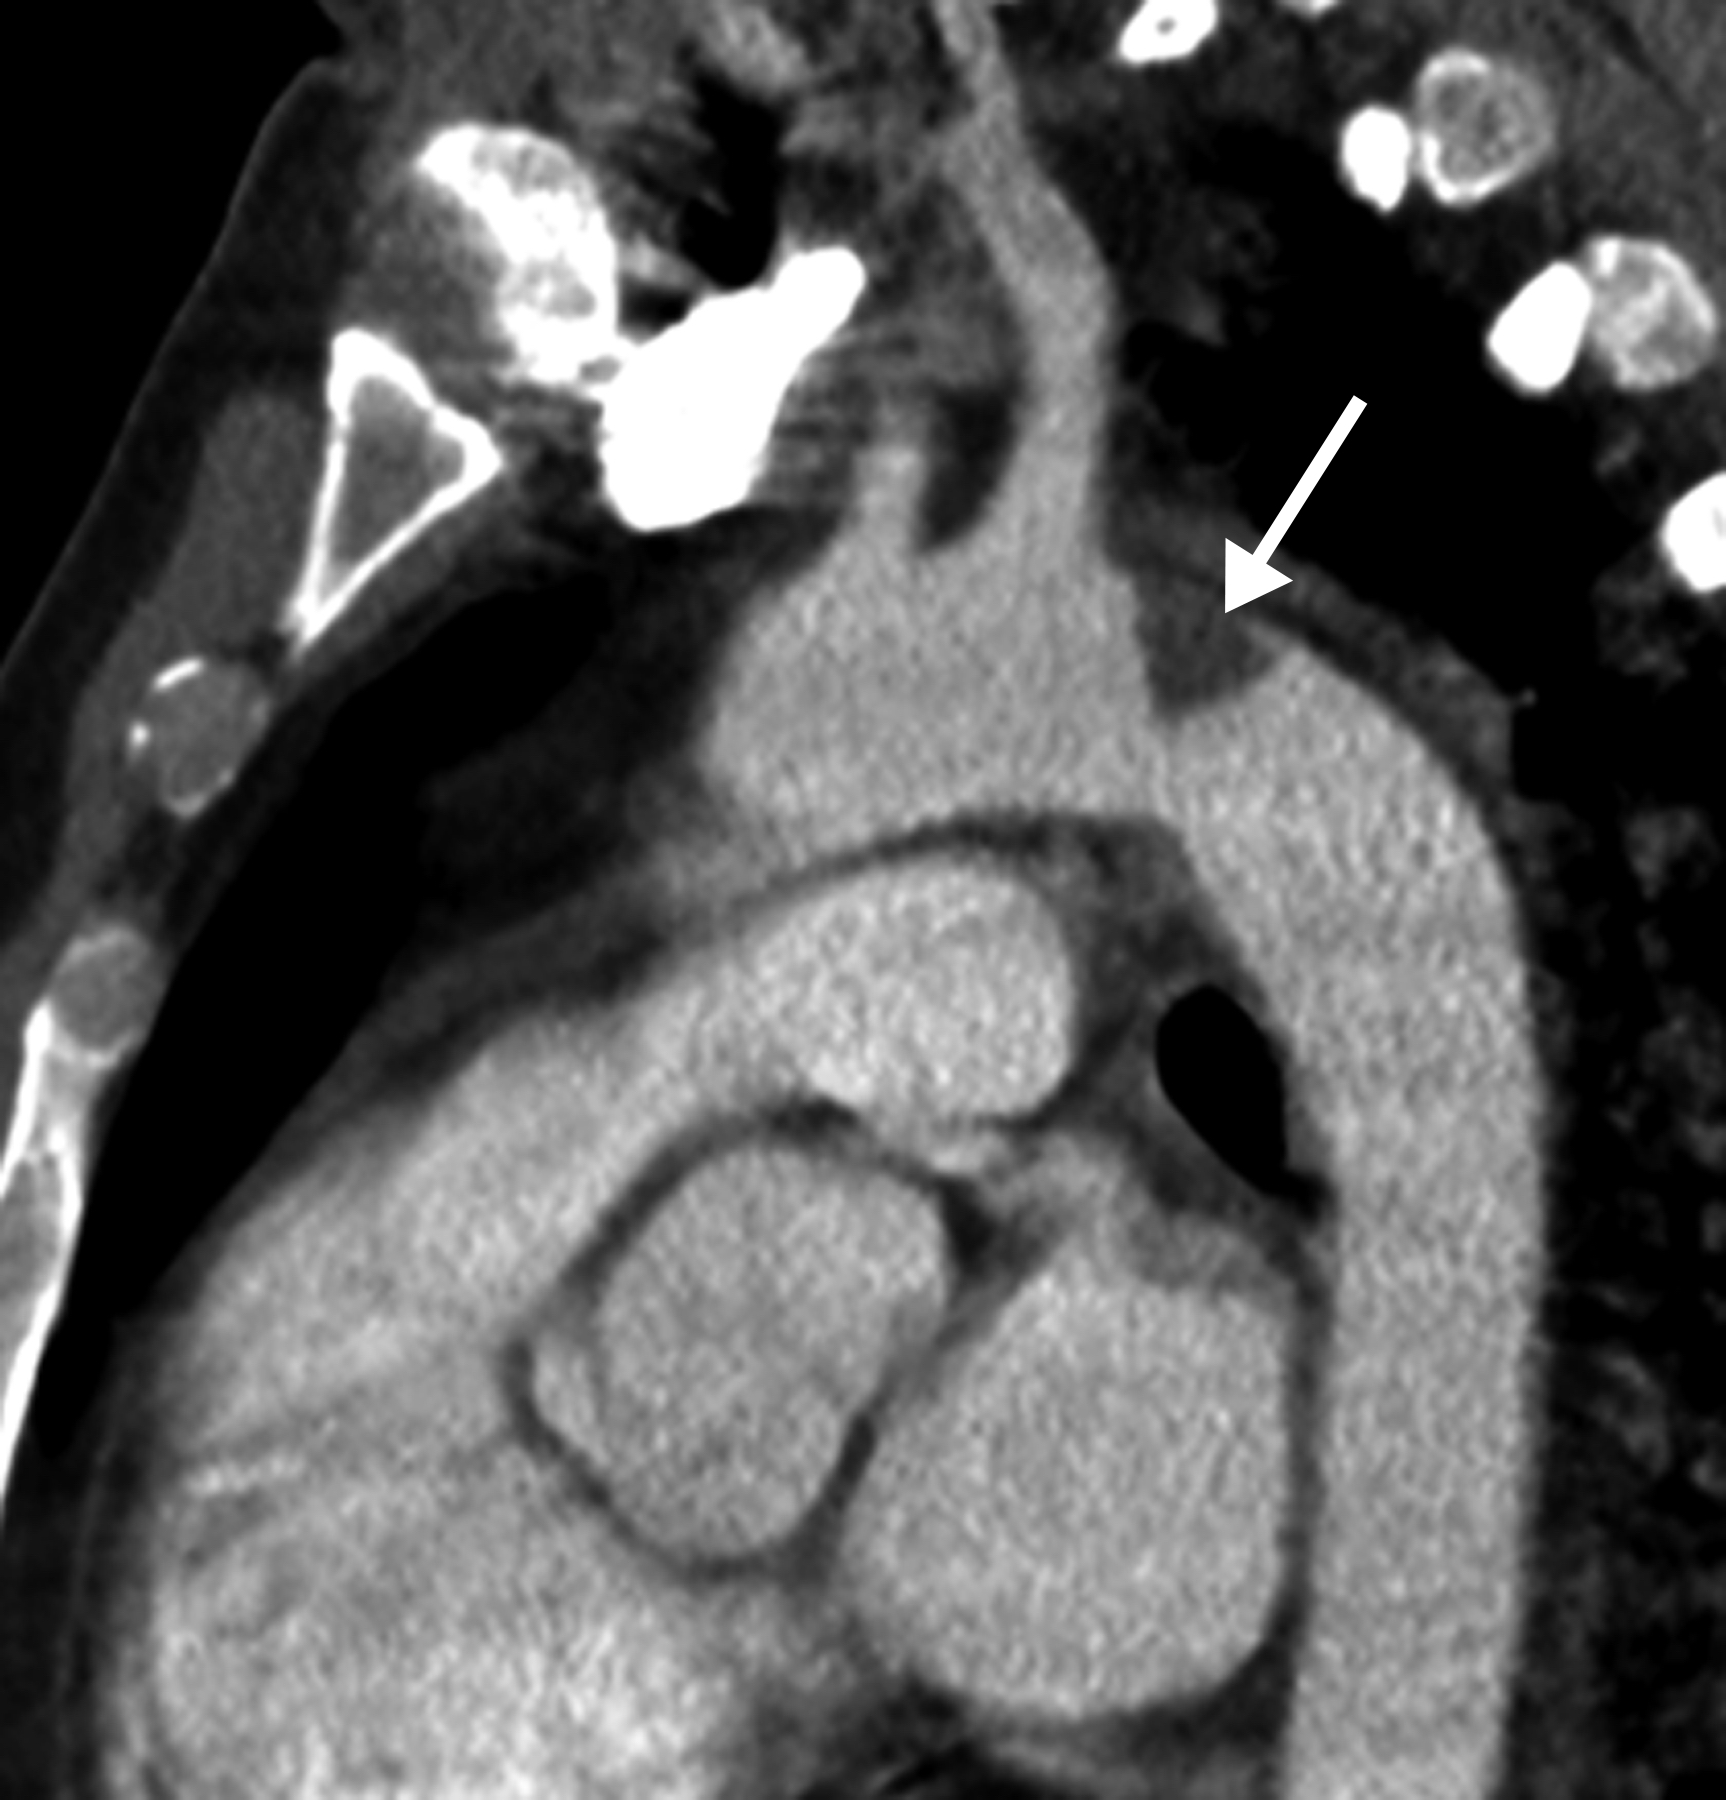

This photo gallery shows the variety of radiological presentations of COVID-19 (SARS-CoV-2) in medical imaging, including computed tomography (CT), radiograph X-rays, ultrasound, echocardiograms and magnetic resonance imaging (MRI). The radiology images show examples of typical COVID pneumonia in the lungs and the numerous complications the virus causes in the body in multiple organs, including the brain, kidneys, heart, abdomen and vascular system.